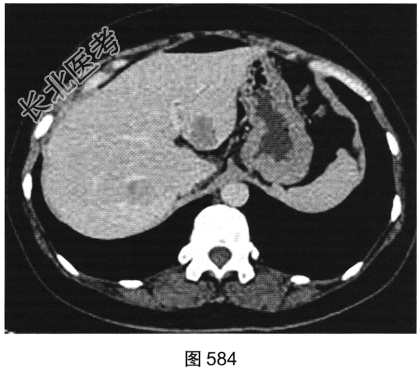

患者女性,38岁,因“间断性下腹部疼痛1周”入院。既往:否认肝炎、结核病史。查体:下腹部压痛。患者行腹部CT检查,见图582~图589。

- 多项选择题1.结合病史及影像学检查结果,可以考虑患者为以下哪些疾病( )

A、肝脏囊肿+附件囊腺瘤

B、肝脏转移瘤+附件囊腺癌

C、肝脏炎性假瘤+附件囊肿

D、肝脏炎性假瘤+输卵管积液

E、肝脏转移瘤+附件囊腺瘤

F、肝脏转移瘤+附件转移瘤